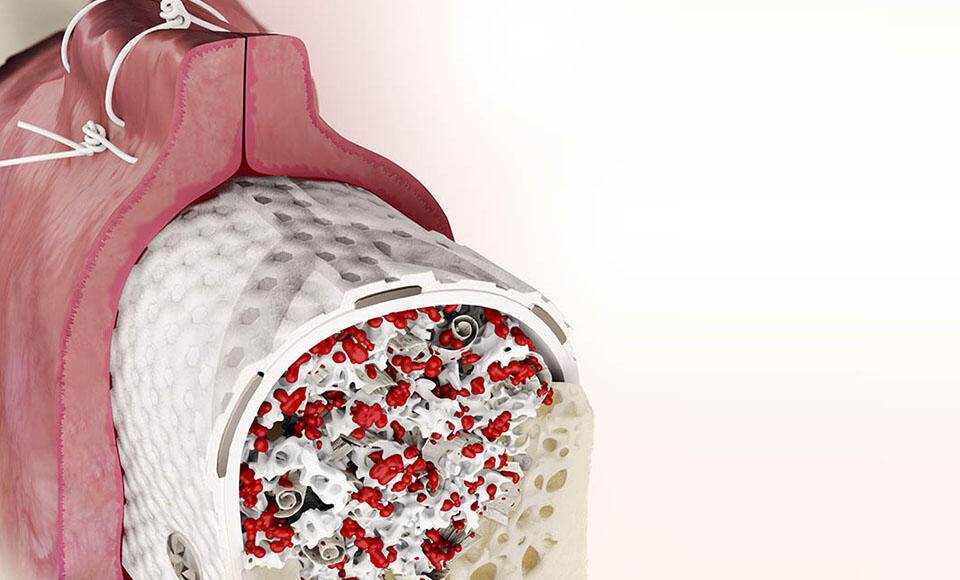

- Il mix fra osso autologo e quello eterologo ad alta porosità, importanti per costruire un rimodellamento osseo congeniale.

Tra gli ultimi interventi effettuati ritengo che la ricostruzione orizzontale e verticale delle creste edentule distali nella mandibola abbia rappresentato il test più probante. Un mix di autologo/eterologo, adeguatamente protetto con membrane RPM-RTM e stabilizzato con il sistema di fissaggio Profix ben chiuso in via primaria è davvero una grandissima soddisfazione per l’operatore ed una grande opzione per il paziente che potrà finalmente riottenere una dentatura stabile supportata dagli impianti.